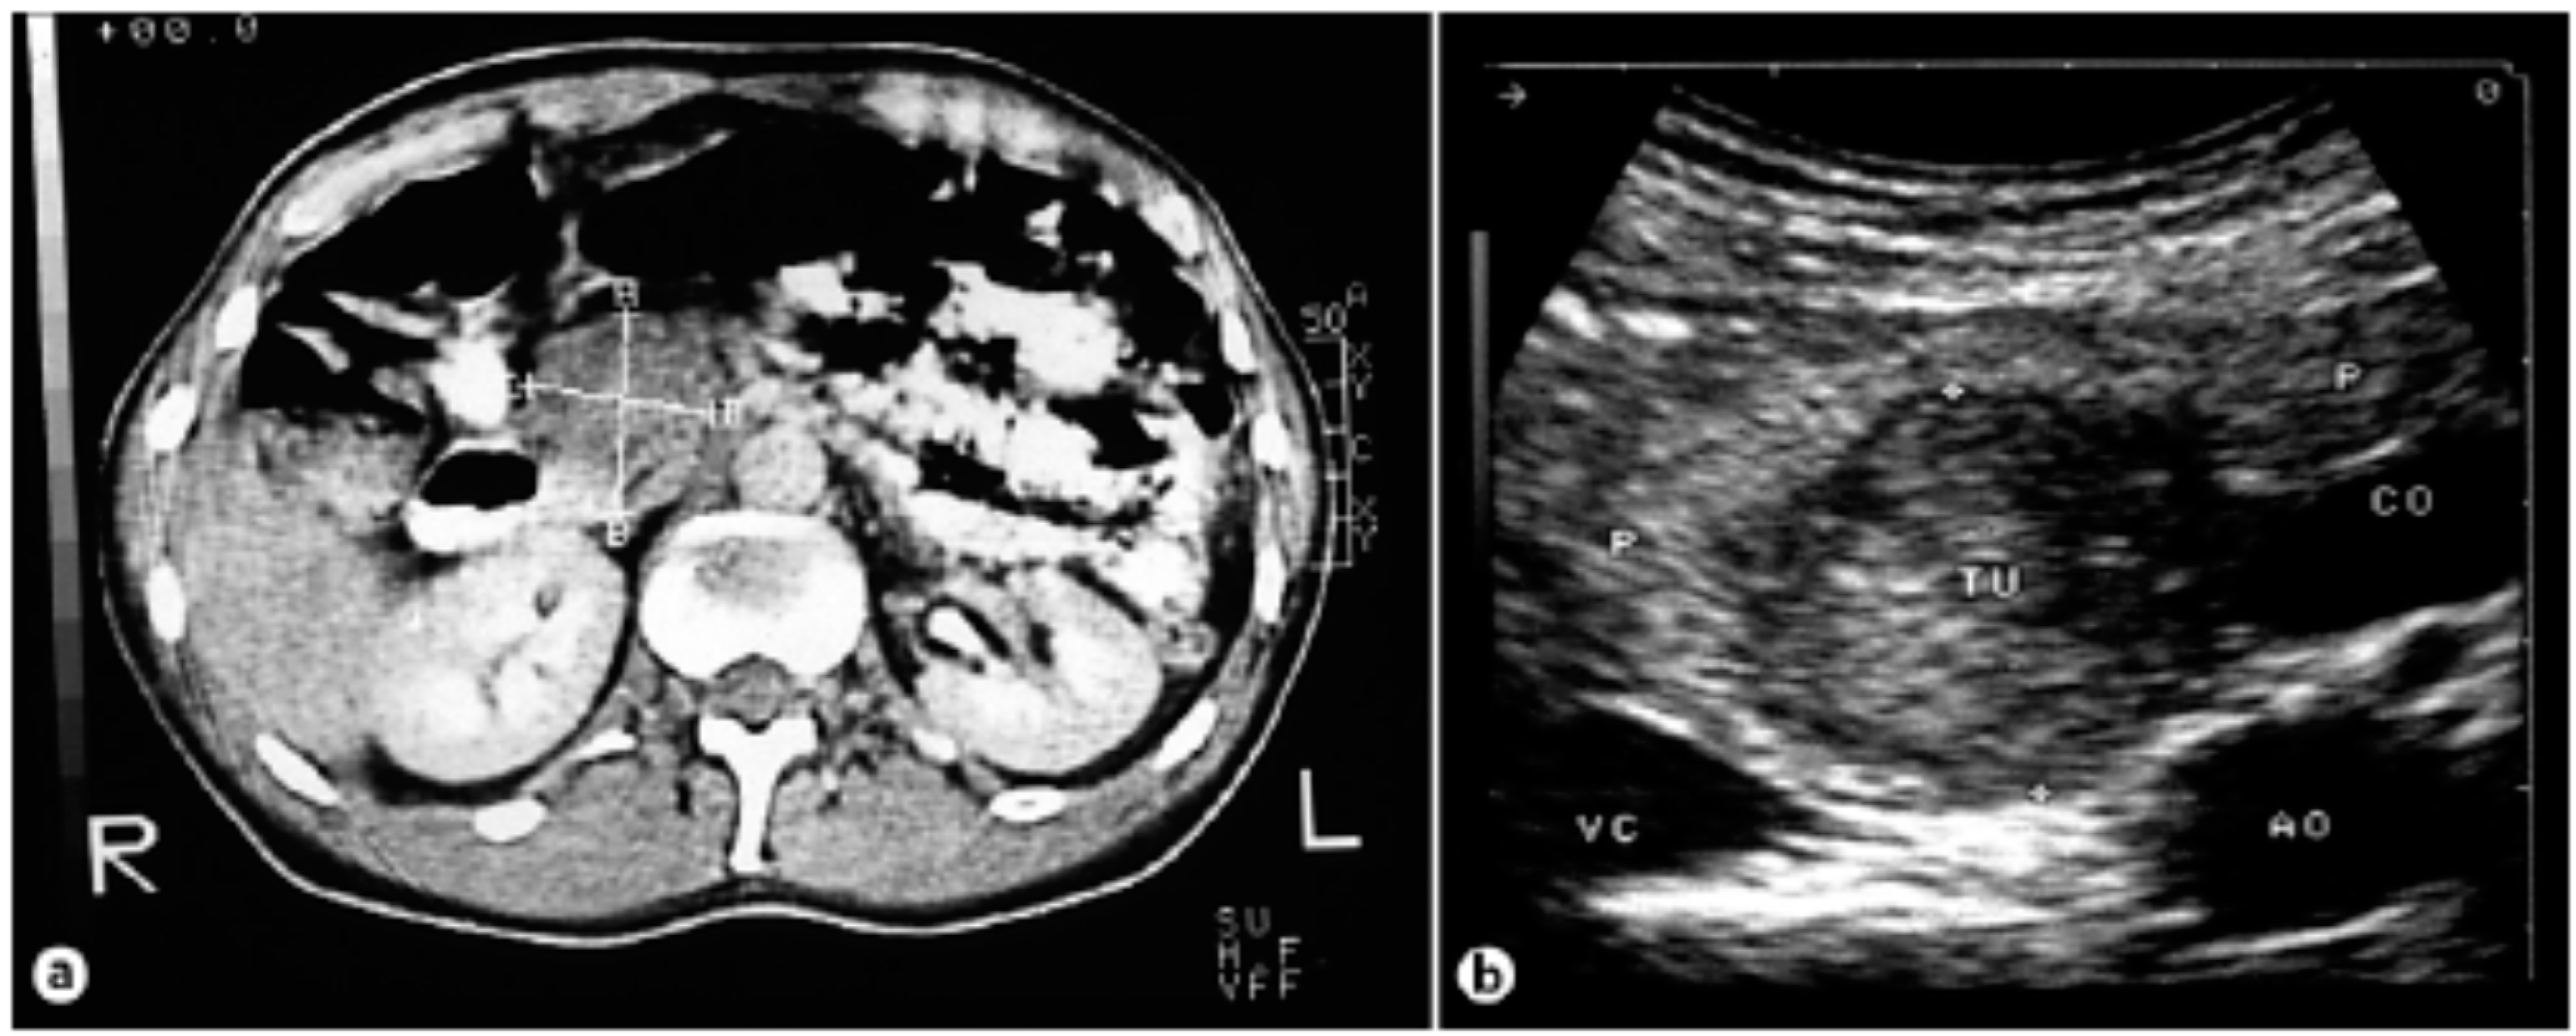

6. Diagnosis